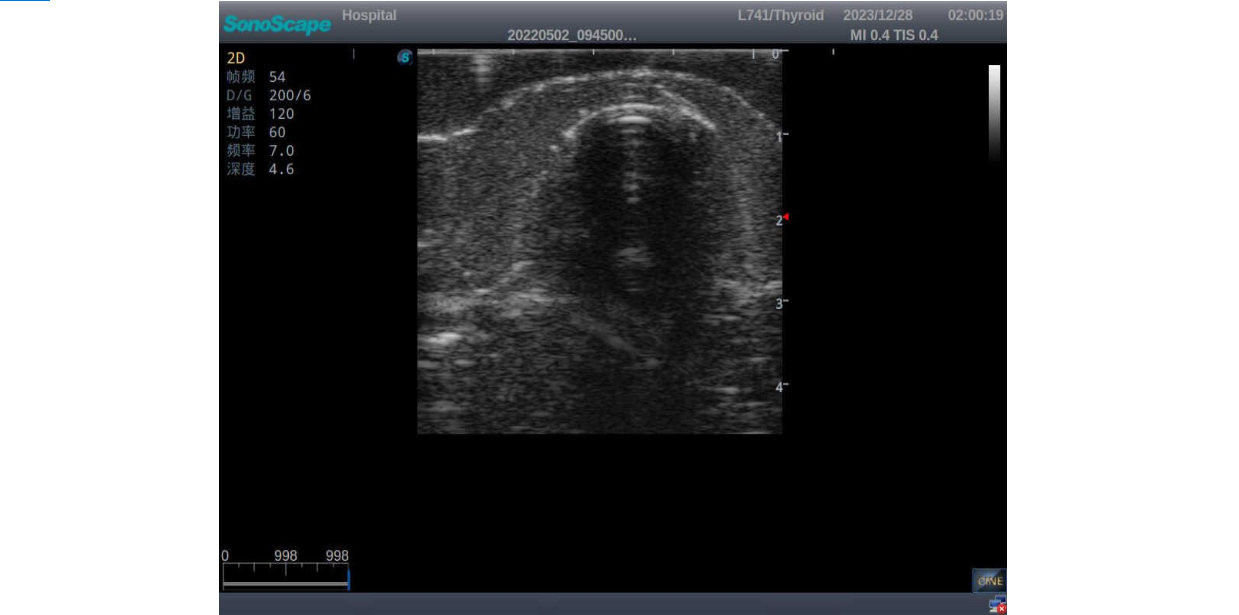

3)       It comes with four (4) thyroid modules and can show five (5) ultrasonic images: normal thyroid, thyroid adenoma, thyroid cancer, nodular goiter, thyroid cyst

Normal thyroid with homogeneous parenchymal echo and well-defined capsule